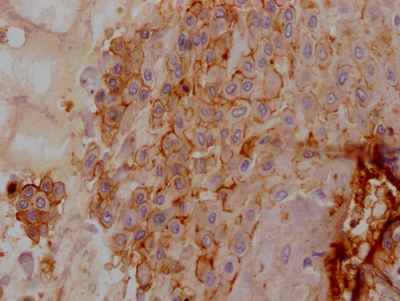

IHC image of CSB-RA440943A0HU diluted at 1:100 and staining in paraffin-embedded human lung tissue performed on a Leica BondTM system. After dewaxing and hydration, antigen retrieval was mediated by high pressure in a citrate buffer (pH 6.0). Section was blocked with 10% normal goat serum 30min at RT. Then primary antibody (1% BSA) was incubated at 4℃ overnight. The primary is detected by a Goat anti-rabbit IgG polymer labeled by HRP and visualized using 0.05% DAB.

CSB-RA440943A0HU